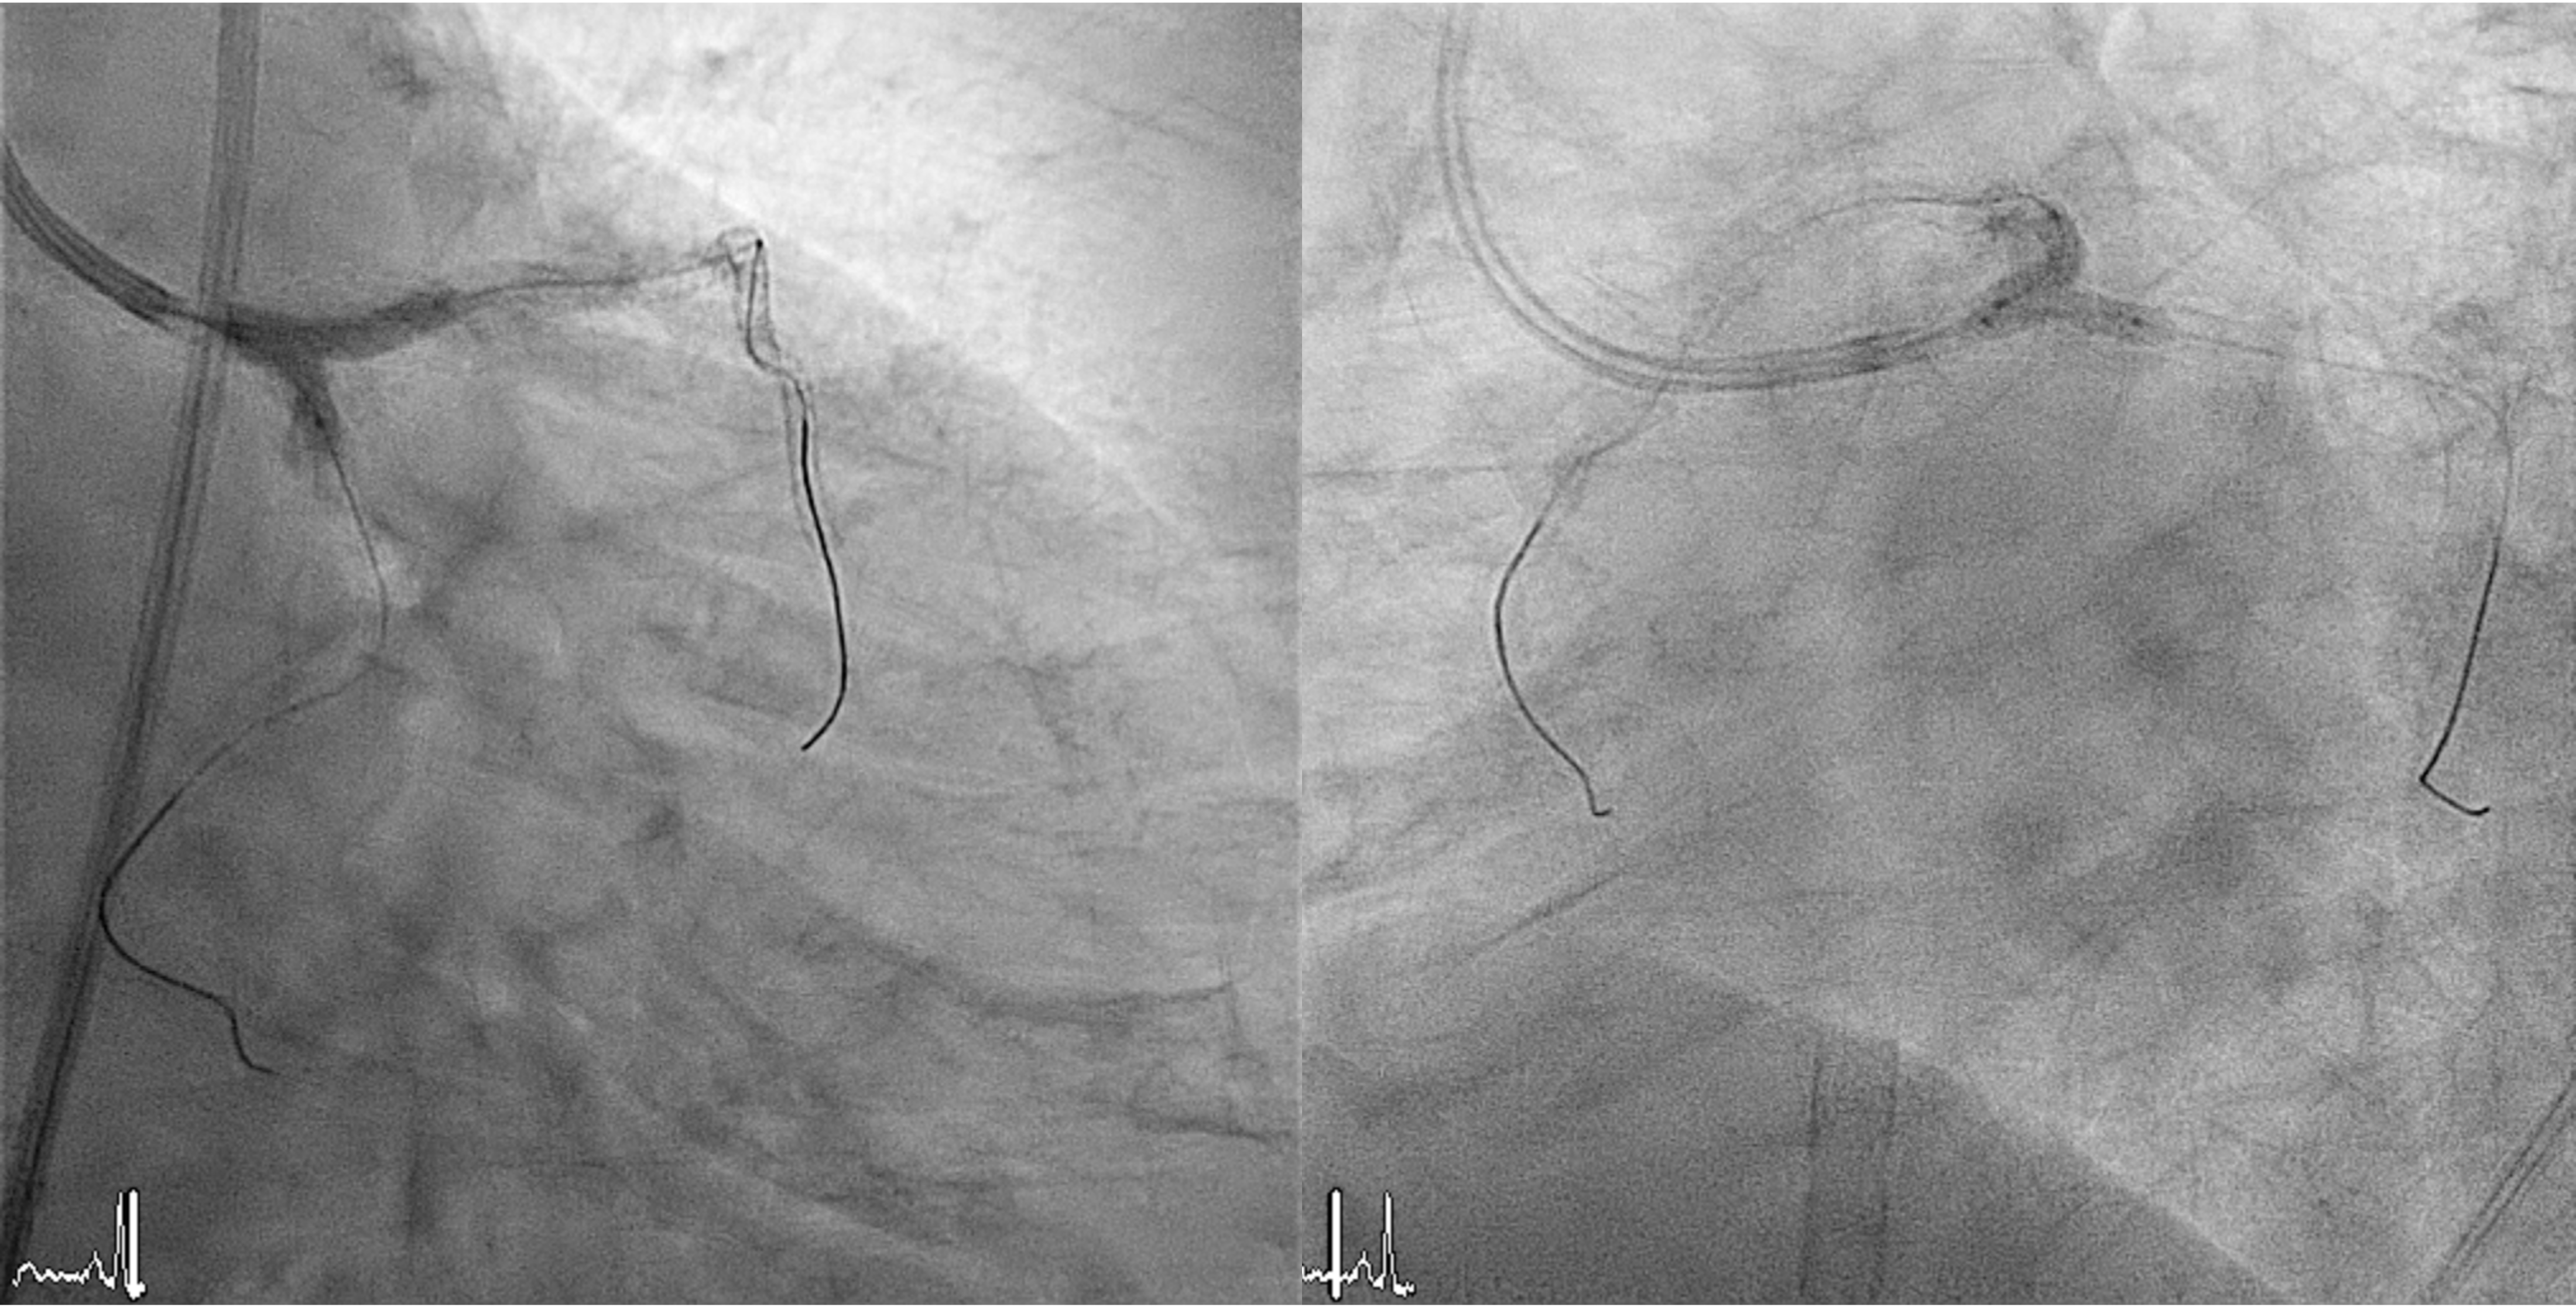

1. Prophylactic mechanical circulatory support with extracorporeal membrane oxygenation (ECMO) was initiated in response to a complex high-risk PCI case that had a high BCIS Jeopardy Score of 12 points.2. Arterial access was obtained via the right femoral artery. A 7 Fr EBU 3.5 guiding catheter was used for the left coronary system, and a 6 Fr JR 3.5 catheter for the right.3. Intravascular ultrasound (IVUS) evaluation revealed long, circumferential calcification with a small luminal area in the LAD (MLA= 2.43mm2), and a prominent calcium nodule extending from the left main to the LCx (MLA= 2.52mm2).4. Owing to severe calcification and an undilatable lesion in the LAD, rotational atherectomy from the proximal to mid segment was performed using a 1.25-mm burr, followed by cutting balloon angioplasty.5. Intravascular lithotripsy (IVL, 3.0 mm) was performed on the proximal LCx and left main bifurcation, combined with cutting balloon angioplasty.6. Double-kissing (DK) crush stenting technique was applied at the left main bifurcation for complex lesion management.7. Finally, three drug-eluting stents (DES) were implanted in the LAD, one in the LCx, and one in the RCA.

22A.mp4

213A.mp4

213B.mp4